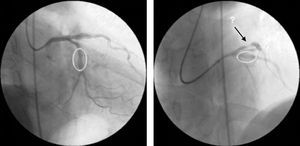

Immediately afterwards there was a drop in arterial blood pressure and the angiogram revealed other new lesions and reduced flow throughout the coronary tree. The patient went into cardiogenic shock and the coronary angiogram showed retention of contrast at various points of the left coronary artery, principally intrastent, and TIMI 0 distal flow (Fig. 4A). Basic and advanced life support maneuvers were begun, a temporary pacing lead was implanted (due to complete atrioventricular block followed by ventricular asystole) and an intra-aortic balloon pump was inserted.

There were various possible causes for this situation including coronary dissection and no-reflow phenomenon, but the most likely in view of the clinical and angiographic context was severe diffuse vasospasm of the coronary tree; intracoronary verapamil was accordingly administered while the patient was still undergoing resuscitation maneuvers and in electromechanical dissociation. This, together with the rest of the pharmacological arsenal and resuscitation efforts, was successful in obtaining TIMI 3 flow (Fig. 4B), sinus rhythm and a rise in blood pressure.

During the latest hospitalization, invasive coronary angiography was repeated, which once again revealed coronary findings that could easily have been interpreted as new lesions, but these resolved after aggressive treatment with intracoronary nitrates (Fig. 6).